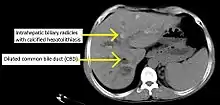

CT scan findings in a case of primary sclerosing cholangitis

PSC is generally diagnosed on the basis of having at least two of three clinical criteria after secondary causes of sclerosing cholangitis have been ruled out:

• cholangiography demonstrating biliary strictures or irregularity consistent with PSC